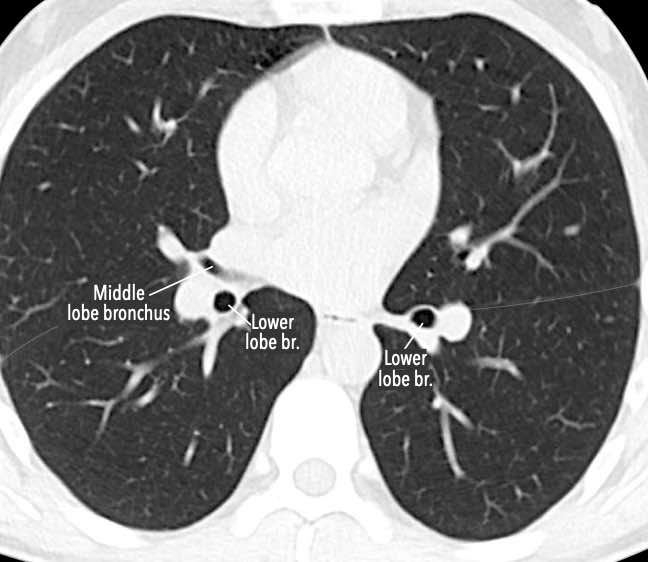

Phế quản trên CT

Cuộn qua các hình ảnh để quan sát khí quản phân chia thành phế quản chính phải và trái, sau đó tiếp tục phân chia thành các phế quản thùy và phế quản phân thùy.